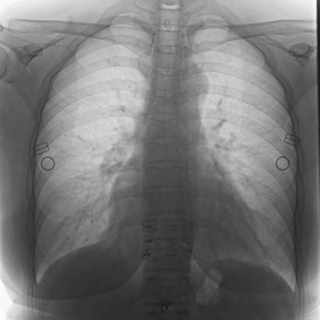

不同于常規(guī)DR只能進(jìn)行平片攝影檢查,普利德多功能動態(tài)平板DRF動靜兼?zhèn)?,可?shí)現(xiàn)大幅面低劑量透視檢查,在日常的體檢工作中,比如胸部及肺部檢查,可對重疊部位病變進(jìn)行可視化觀察及多角度旋轉(zhuǎn)體位,發(fā)現(xiàn)疑似病灶可瞬時完成高清點(diǎn)片,顯著提高診斷的準(zhǔn)確性。

動態(tài)采集幀率最高可達(dá)30幀/s,影像細(xì)膩流暢,便于醫(yī)生對細(xì)微病變的觀察。17×17英寸大幅面成像,在透視過程中能對患者的胸部腹部等部位實(shí)現(xiàn)大范圍覆蓋,便于從整體上觀察組織信息,更加全面且精準(zhǔn)的捕捉病灶。